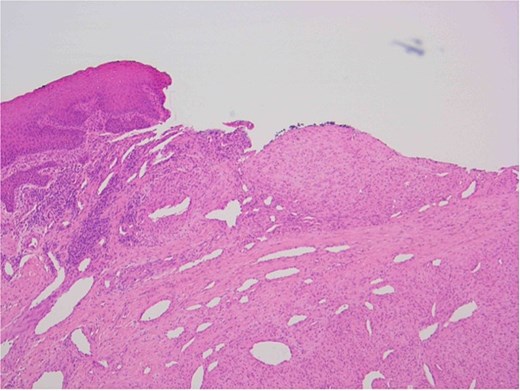

The patient underwent a biopsy of the lesion. Histopathological analysis revealed spindle cell proliferation arranged in a fascicular growth pattern, dilated hemangiopericytoma-like vessels, and a central myeloid nodule. Immunohistochemical staining was positive for smooth muscle actin (SMA), with no evidence of cellular atypia (Figs 5–7).

Ulcerated area with underlying bland spindle cell proliferation showing fascicular growth impression of cellularity involving vascular wall – haemangiopericytoma-like architecture (central).